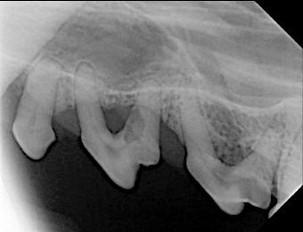

We are very excited to announce our Digital Dental Xray machine. We now have a wonderful way to complete our comprehensive dental care for our pets.

We can’t treat what we can’t see, but your pet can certainly feel when something is wrong!

We can assess all the teeth in the mouth, looking at the roots and the bone surrounding the tooth to see if more treatment is needed.